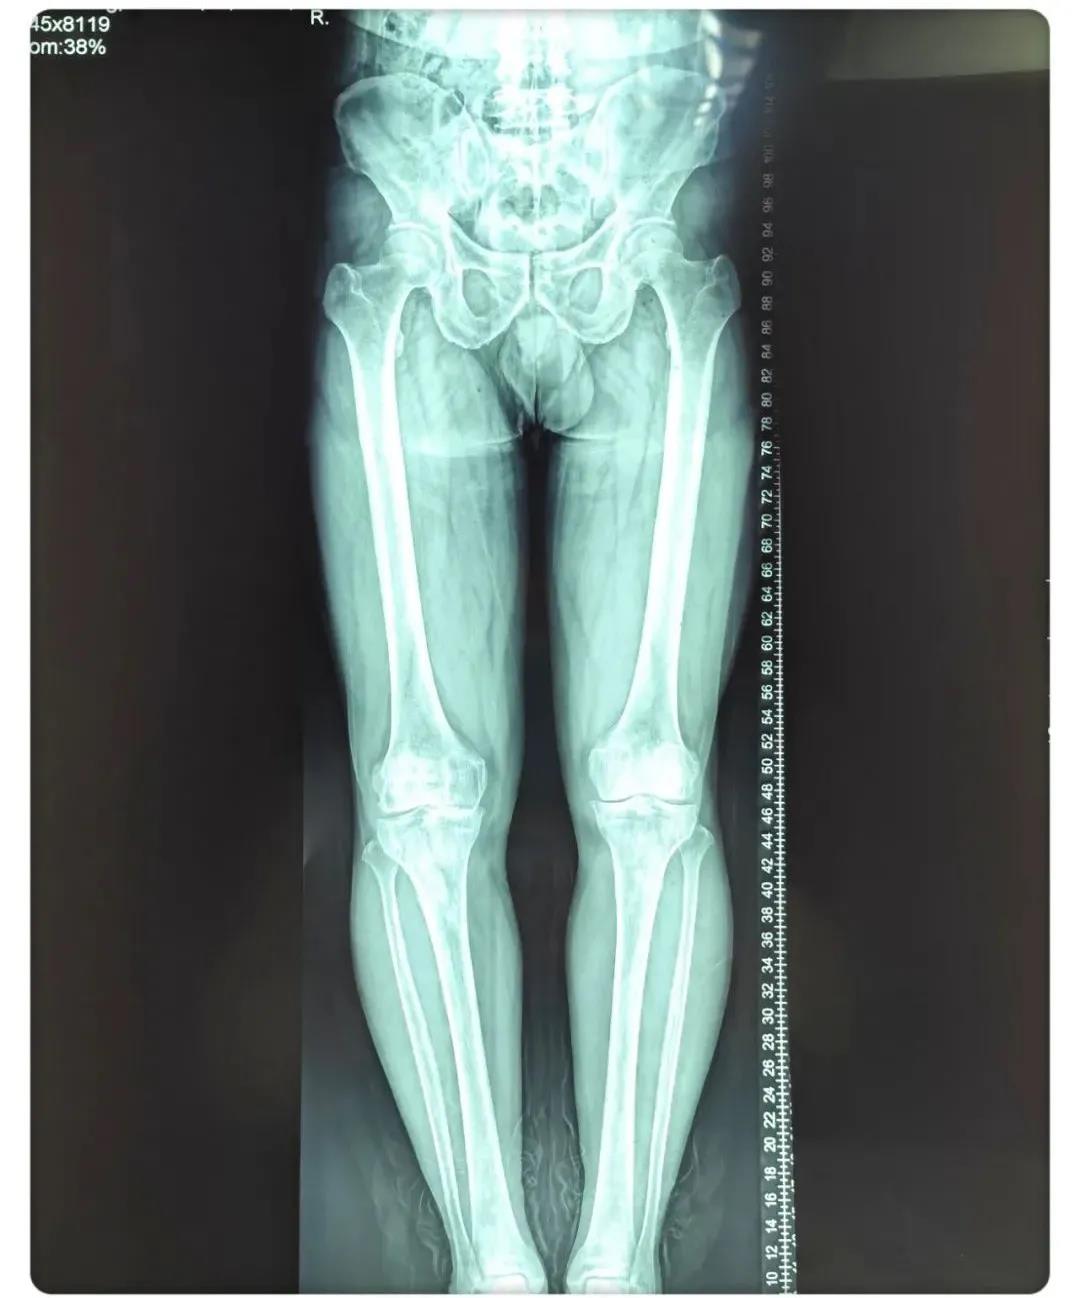

術(shù)前患者腿部X線片

術(shù)后患者X線片